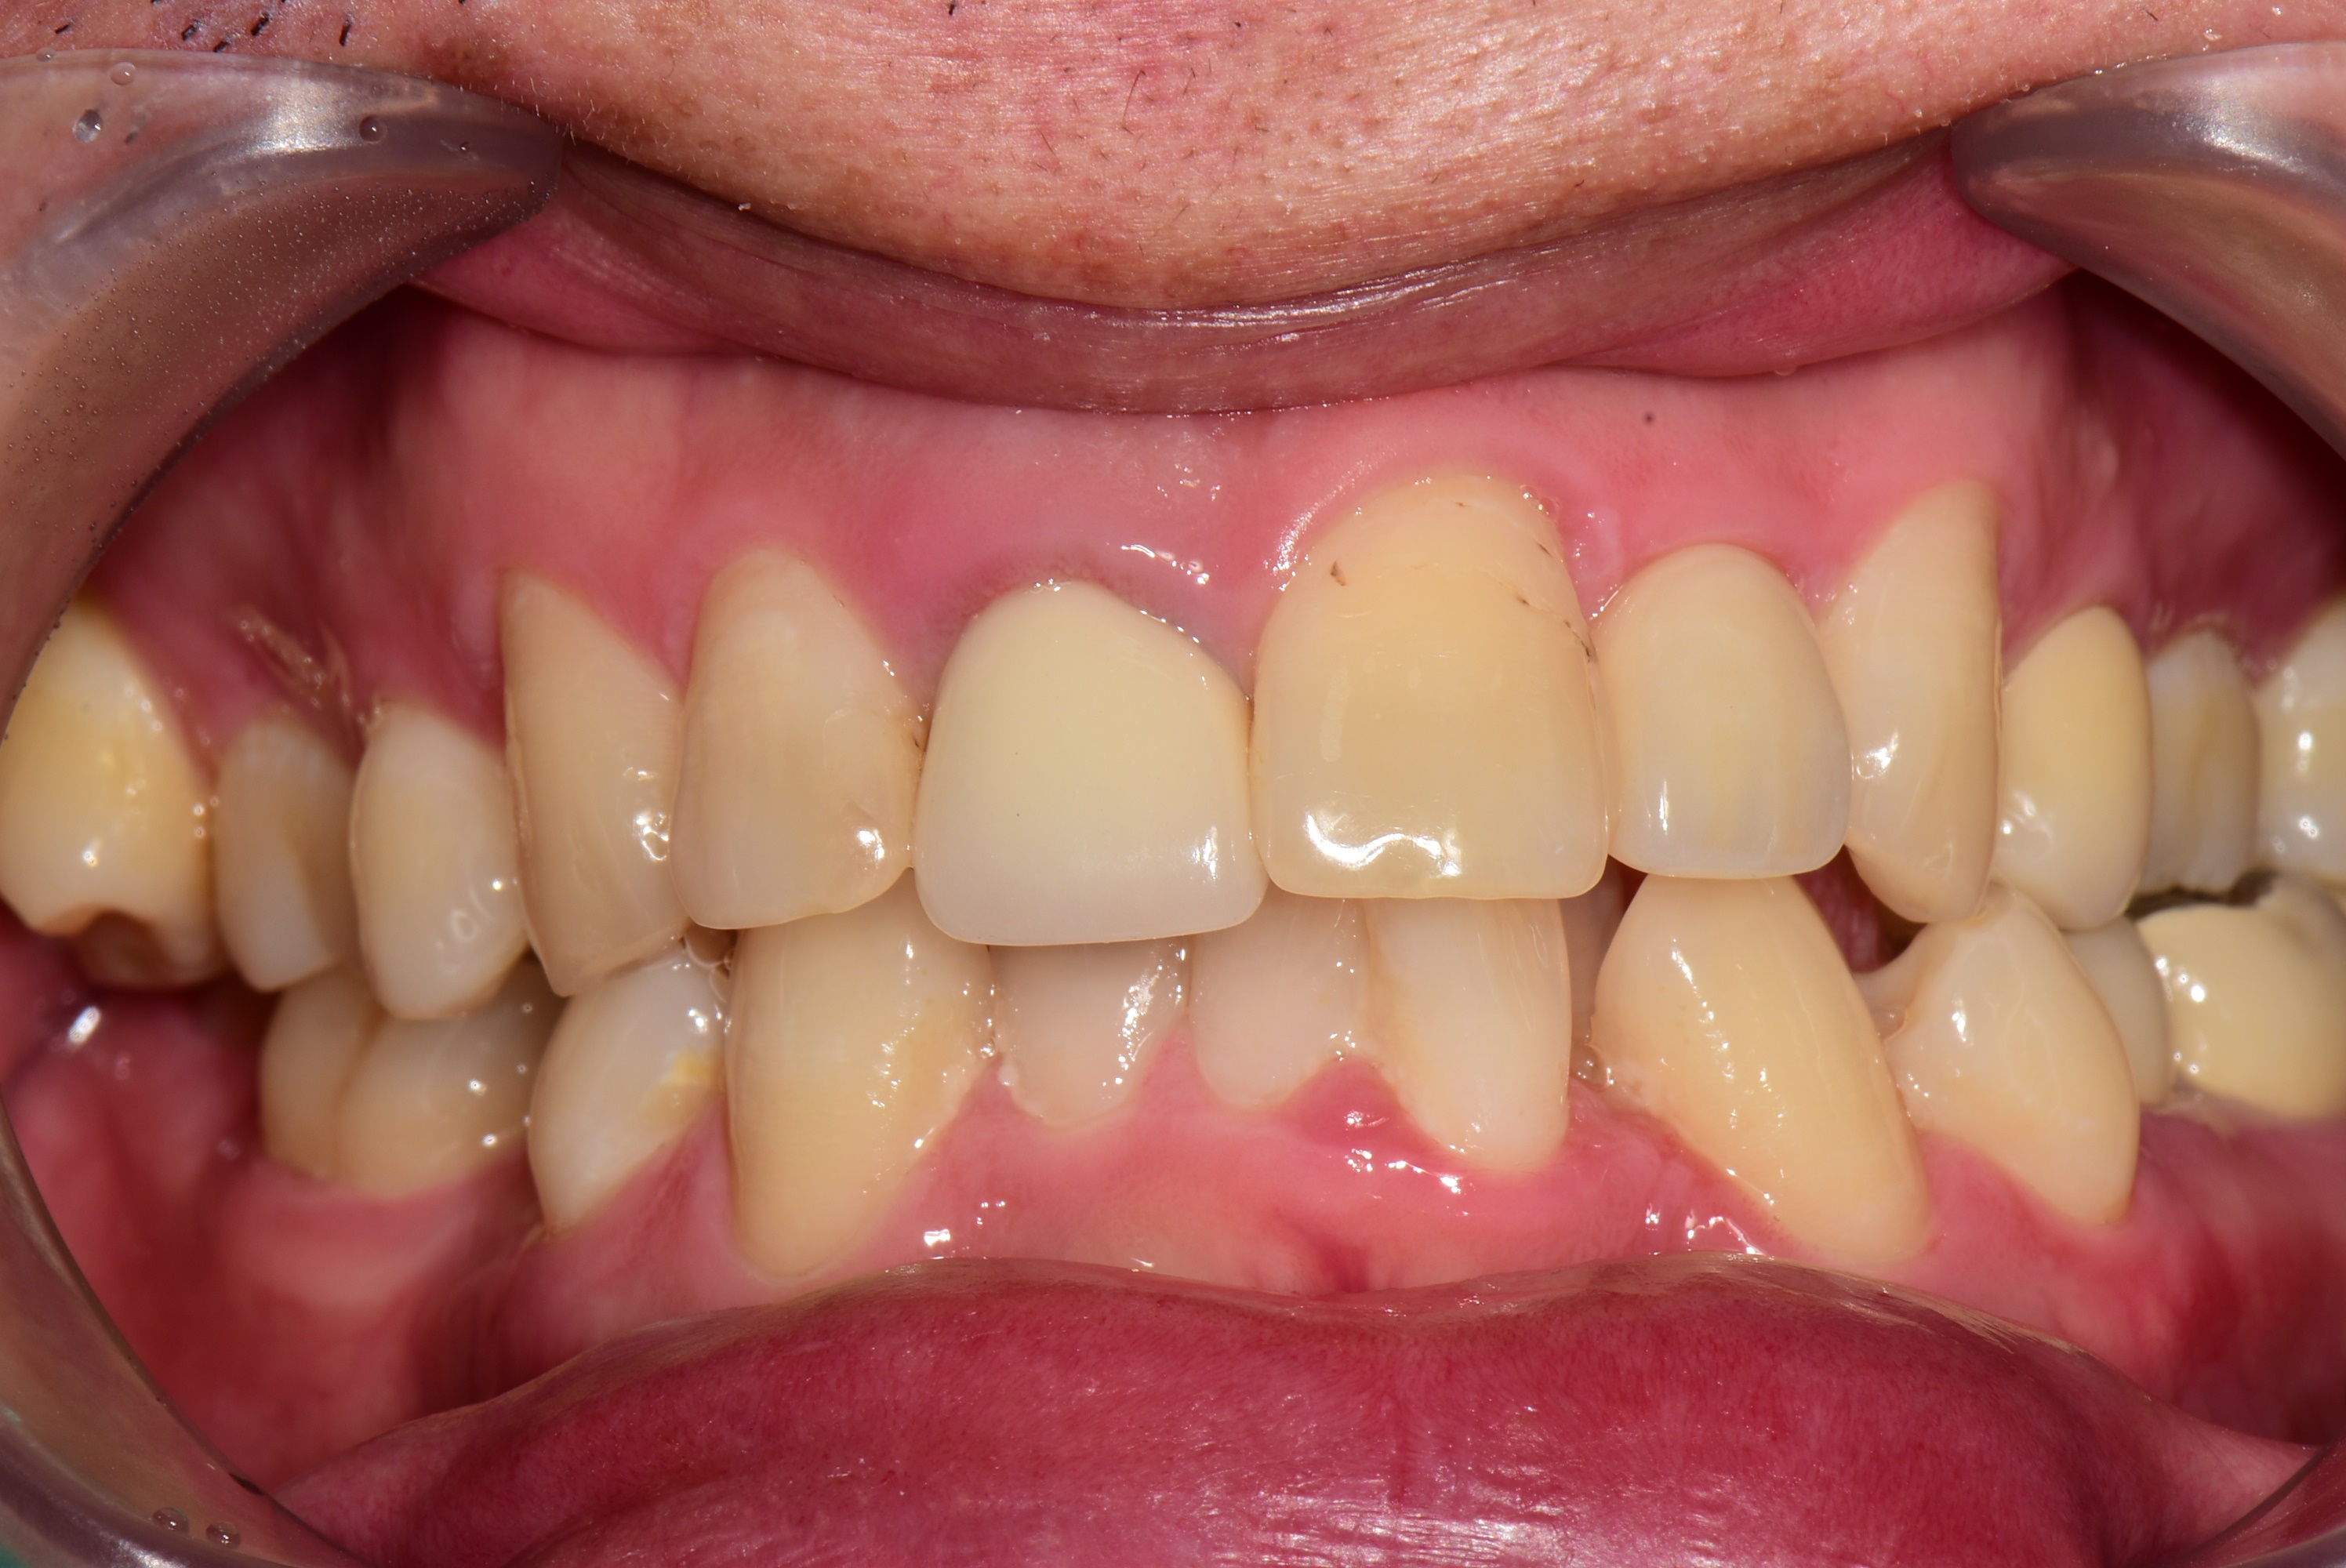

아래는 3개월 후 최종 보철 후 사진입니다.